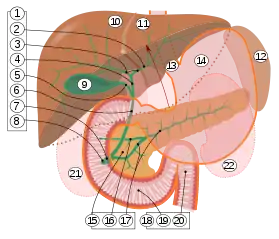

9. Gallbladder.

10–11. Right and left lobes of liver.

12. Spleen.

13. Esophagus.

14. Stomach.

15. Pancreas: 16. Accessory pancreatic duct, 17. Pancreatic duct.

18. Small intestine: 19. Duodenum, 20. Jejunum

21–22. Right and left kidneys.

The front border of the liver has been lifted up (brown arrow).[1]